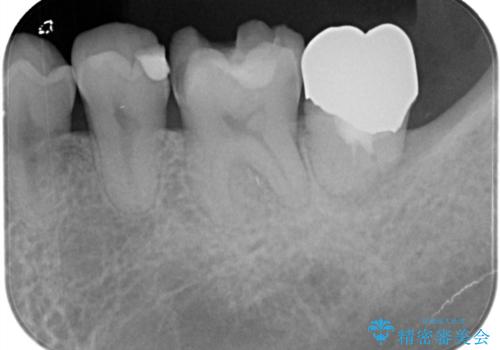

- 金属の詰め物が外れたことを主訴に来院されました。

隣の歯もむし歯を認め、セラミックインレーとセラミッククラウンにて治療を行なっております。

最後方臼歯に関しては治療介入の希望はされませんでした。